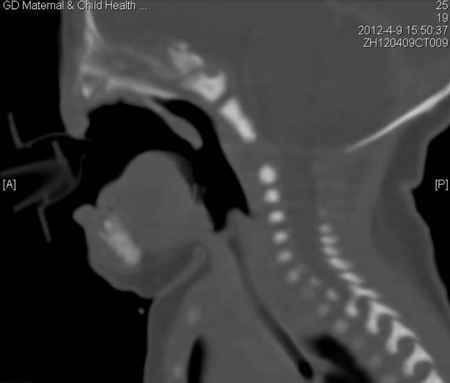

A healthy 40-year-old, gravida 5 and para 5, woman delivered a male infant weighing 2.89 kg by spontaneous vaginal delivery at term. There was neither a family background of congenital malformations nor a history of any medications during the pregnancy. The prenatal course was uncomplicated. On examination, the baby showed absence of the nose, nasal root, nasal pits; microphthalmia, auris dextra microtia, right side anorchia, small penis, high arched palate, hypoplasia of bilateral maxillary sinus and ethmoid sinus (Fig. 1-3). There were longitudinal ridge-like protuberances in the mid-face. Shortly, the infant was transferred to the neonatal intensive care unit for further evaluation and monitoring. The baby had severe shortness of breath which was relieved by an oropharyngeal tube. Karyotyping performed was 46 XY. The dyspnea and tachypnea greatly improved one month later and the baby adapted to oral breathing and feeding simultaneously. Further work-up including echocardiogram, CT brain, and blood chemistry, all were normal.

Figure 3: CT scan showing high arched palate, nostril atresia, the hypoplasia of bilateral maxillary sinus and ethmoid sinus |